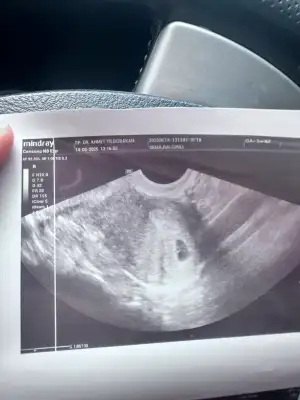

Kızlar keseme bakar mısınız normal mi 5+2 bugün doktor dedi bebek var içinde 10 gün sonra kalp atışına çağirdi

• IMG_3584.webp

IMG_3584.webp

32,7 KB · Görüntüleme: 23